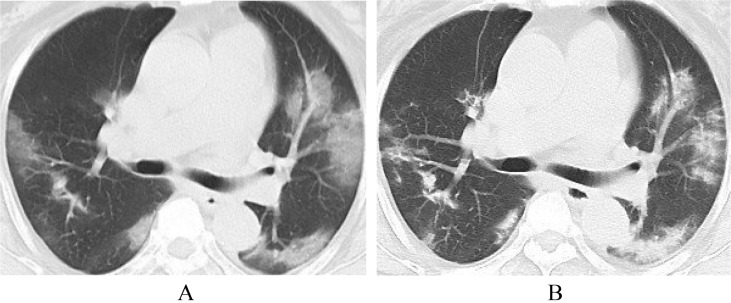

In most patients who recovered from COVID-19, the involvement range of pulmonary lesions reached a peak and then gradually decreased 10 days after the onset of the initial symptom. The guidelines [9] reviewed the chest CT data of 83 patients: ① Ultra-early stage (patients without clinical manifestation, negative laboratory test but positive throat swab for 2019-nCoV, 8.4% in a total of 83 cases). The main imaging manifestations were single, double or scattered focal ground glass opacity, nodules located in central lobule surrounded by patchy ground glass opacities, patchy consolidation with air-bronchogram, which was mainly distributed in the middle and lower pleura. ② Early stage (1–3 days after the onset of the initial symptom, 54.2% in a total of 83 cases). Single or multiple scattered patchy or agglomerated ground-glass opacities were showed, separated by honeycomb-like or grid-like thickened of interlobular septa. ③ Rapid progression stage (3–7 days after the onset of the initial symptom, 20.5% in a total of 83 cases). The CT findings were a fusion of large, light consolidation with air bronchogram. ④ Consolidation stage (7–14 days after the onset of the initial symptom, 31.2% in a total of 83 cases). CT imaging showed multiple patchy consolidation, and the range was slightly smaller than that of the previous stage. ⑤ Dissipation stage (2–3 weeks after the onset of the initial symptom, 20.5% in a total of 83 cases). The CT findings were patchy consolidation or strip-like opacity. As time goes on, it showed grid-like thickening of interlobular septa, thickening and strip-like twist of bronchial wall and a few scattered patchy consolidations. Shi et al. [13] divided 81 patients into 4 groups according to the interval between initial symptoms and CT examination. ① Group 1 (patients without symptoms, n = 15) mainly presented unilateral (60%), polycentric (53%) ground glass opacity (93%); ② Group 2 (within 1 week of symptom onset, n = 21) mainly presented bilateral (90%), diffuse (52%) ground glass opacity (81%). ③ Group 3 (more than 1 week less than 2 weeks after the onset of the initial symptom, n = 30) showed ground glass opacity (57%) reduced, consolidation and mixed lesions appeared (40%). ④ Group 4 (more than 2 weeks less than 3 weeks after the onset of the initial symptom, n = 15) showed that consolidation and mixed lesions (53%) were the main features and ground glass opacity (33%) continued to reduce. All of the above studies indicated that, with the progression of disease, the lesions tended to be both-lungs and diffuse distribution and the ground glass opacity gradually decreased, while the consolidation shadow gradually increased (Fig. 7, Fig. 8 ).

Fig. 7.

41-year old male. A, CT shows no obvious abnormalities in both lungs; B, five days later, CT shows new GGO in the lower lobes of both lungs.

Fig. 8.

56-year old female. A, CT shows ground glass opacity both lungs; B, five days later, CT shows ground glass opacity decreased and consolidation increased.